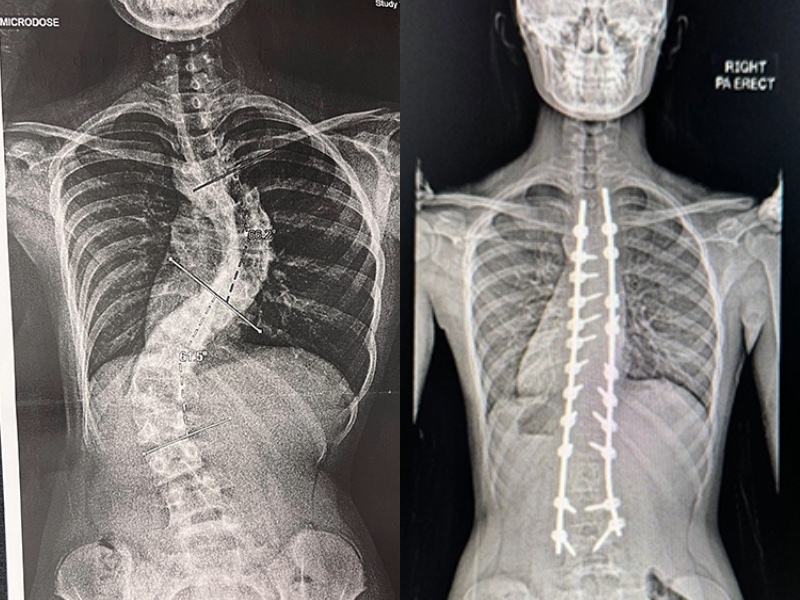

Vera discovered her spark in sports. Genetically well endowed with height – both her parents are tall – she gravitated towards netball. By Primary Four, she had grown rapidly, becoming the tallest in her class. But just as things seemed to be going well, her family noticed something unusual – one of Vera’s shoulders was noticeably higher than the other. A prompt appointment confirmed the diagnosis: adolescent idiopathic scoliosis of severe magnitude. Her spine was growing sideways, twisting into an S-shape. The curves even made her shorter than she ought to have been.

Vera’s scoliosis treatment began immediately with a rigid brace, usually prescribed for curves between 20 and 40 degrees. Success required discipline: at least 13 hours of wear per day. Vera tried her best, but her competitive streak often kept her longer on the court than in the brace. At her follow-up, the curves had progressed aggressively to 65 degrees. She had just entered Primary Six.

They chose health first, and the scoliosis surgery went ahead as planned. The first few days were not as difficult as Vera had imagined. Her resilience shone through, and our team placed her on an accelerated rehabilitation pathway. Her parents became her greatest cheerleaders, celebrating each small win. Vera was discharged just four days after surgery.